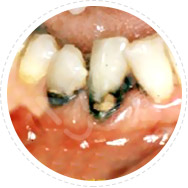

• 龋洞、牙冠蛀损

麦芽树脂补牙

去除龋坏的牙齿后,选用树脂材料对牙洞进行填充,麦芽树脂补牙美观耐磨、使用长久、媲美真牙!

适应症:龋洞、牙冠蛀损